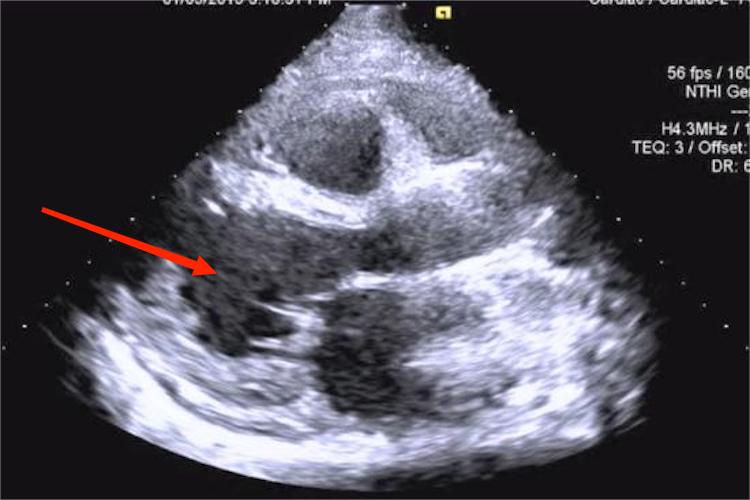

超声心动图检查:可正常,也可显示左心室增大,室壁运动减低,左心室收缩功能减低,附壁血栓等。合并心包炎者可有心包积液。